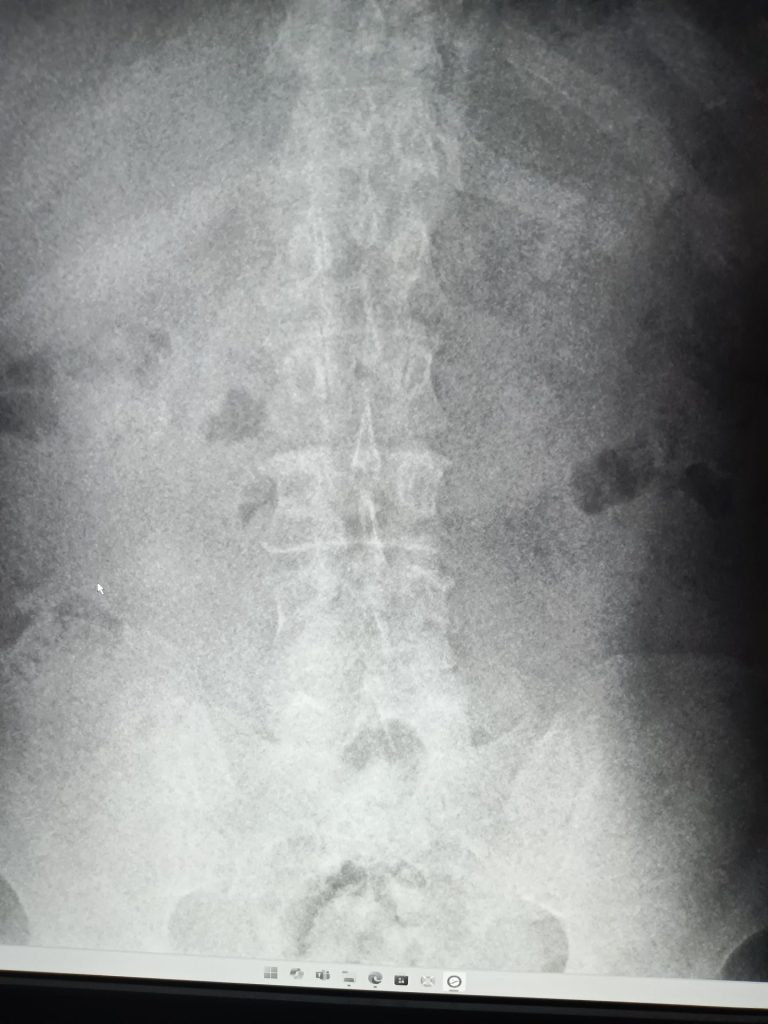

線量不足が原因で不鮮明な画像となっているX線写真(2枚目)と、適切な方法で撮影したX線写真(2枚目)

医師は左の画像で診断していたたため、右のように鮮明に撮影できるよう具体的な方法をレクチャーし、徐々に改善に向かっています。